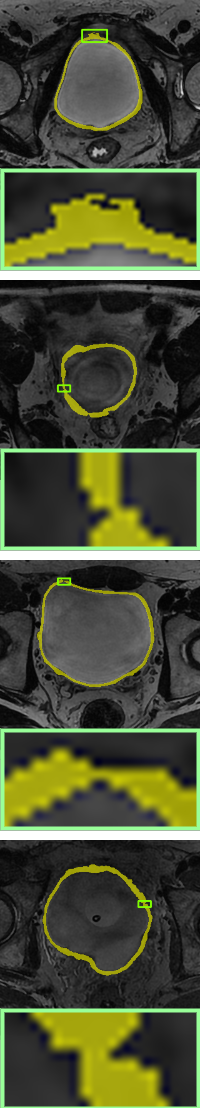

Ground-truth

Without-topo

PH[ph]

Proposed WT

We compare the results of no topological constraints (without-topo), topological constraints without width (PH), and width-aware topological constraints (WT) applied to a number of data-driven models for relevant applications. As can be seen in Table 3, our proposed method (rows with gray background) shows superior performance. Specifically, the improvements in volumetric demonstrate that our method has more accurate result in a pixel-level sense, while the improvements on topology-based metrics demonstrate that WT energy has an overall more precise prediction and topological similarity. For boundary-based indicators, WT performs better compared to PH in most cases due to the width information. The corresponding visualization is given in Fig. 10 and Fig. 11. From the visualization results, it can be seen that in data-driven image segmentation models, no topological constraints will produce obvious topological errors, even if its segmentation results have high accuracy. When constraining topological consistency using persistent homology methods, it may be possible to connect very thin lines to ensure connectivity or a consistent number of holes. We improve the PH method by smoothing the critical points in there structuring elements neighborhood, which can preserve the width information while constraining the topological properties to be consistent.